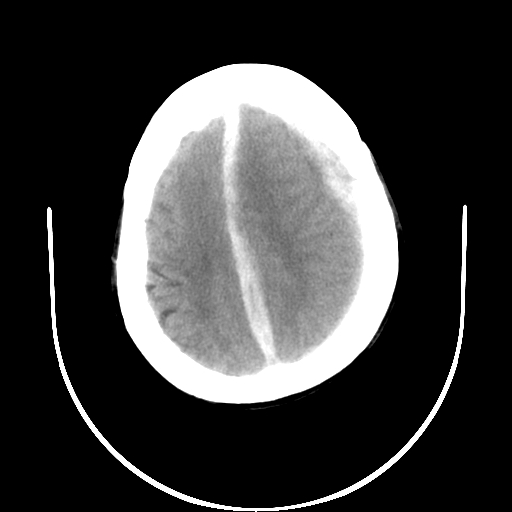

以下是引用gaoshengjiang在2007-10-7 9:18:00的发言:[br]左枕叶脑出血,左额颞顶部及纵裂硬膜下血肿,蛛网膜下腔出血,右颞叶脑梗塞。出血原因:患者年龄较大可能为动脉硬化或血管畸形?建议进一步临床检查。